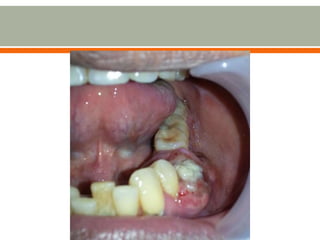

 Presence of mass

 Presence of swelling

 Usually asymptomatic

o If infection enters, the swelling

becomes painful and rapidly

expands

o Initially swelling is round and hard

o Later part of the wall is resorbed

leaving a soft fluctuant

swelling, bluish in color, beneath the

mucous membrane

 The radicular cyst is usually symptomless and detected incidentally on

plain OPG while investigating for other diseases. However, as some of

them grow, they can cause mobility and displacement of teeth and once

infected, lead to pain and swelling, after which the patient usually

becomes aware of the problem. The swelling is slowly enlarging and

initially bony hard to palpate which later becomes rubbery and fluctuant.

 Presence ofmass  Presence of swelling